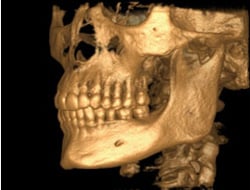

We have the latest, and most advanced 3-D Imaging technology in our new state of the art facility. Three dimensional imaging for dental implant placement provides for precise diagnosis and control of implant placement. In many cases, Dr. Gould will recommend a 3-D scan (also known as a Cone Beam Computed Tomography scan) to facilitate precise treatment planning of your dental implant.

We have the latest, and most advanced 3-D Imaging technology in our new state of the art facility. Three dimensional imaging for dental implant placement provides for precise diagnosis and control of implant placement. In many cases, Dr. Gould will recommend a 3-D scan (also known as a Cone Beam Computed Tomography scan) to facilitate precise treatment planning of your dental implant.

Dr. Gould can virtually plan your dental implant on the computer to ensure ideal placement and esthetics. We can then utilize your virtual plan to place your implant using guided surgery. Ask us about our 3-D Implant Imaging capabilities!

Dr. Gould can virtually plan your dental implant on the computer to ensure ideal placement and esthetics. We can then utilize your virtual plan to place your implant using guided surgery. Ask us about our 3-D Implant Imaging capabilities!